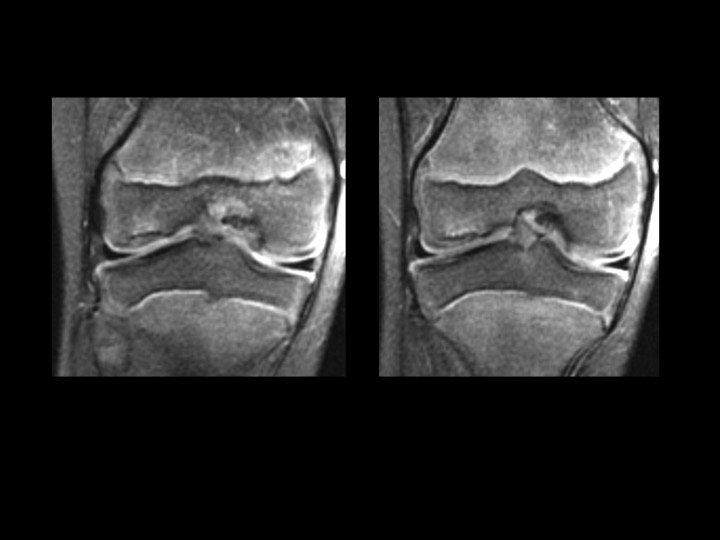

9M fell 3 weeks ago, evaluate osteochondral lesion

The subchondral cortical flattening and minimal subchondral bright T2 signal with smooth, relatively thick overlying articular cartilage is not related to the injury 3 weeks prior. I considered possible chronic stable OCL, but I believe this looks like the normal variant ossification in the attached article. Any dissent? Reference article.

normal developmental irregular ossification lateral femoral condyle